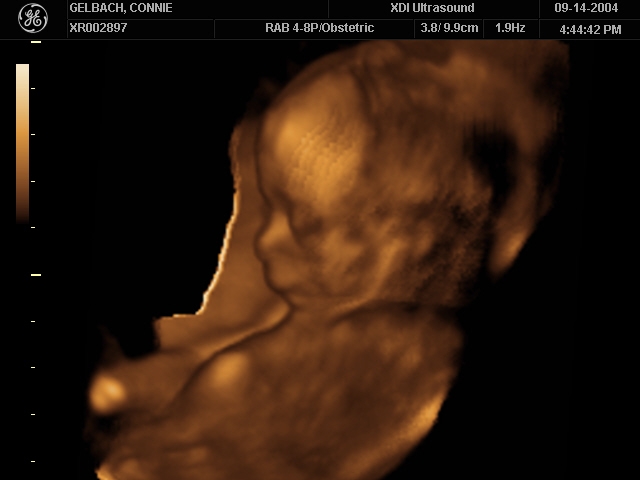

Sonograms